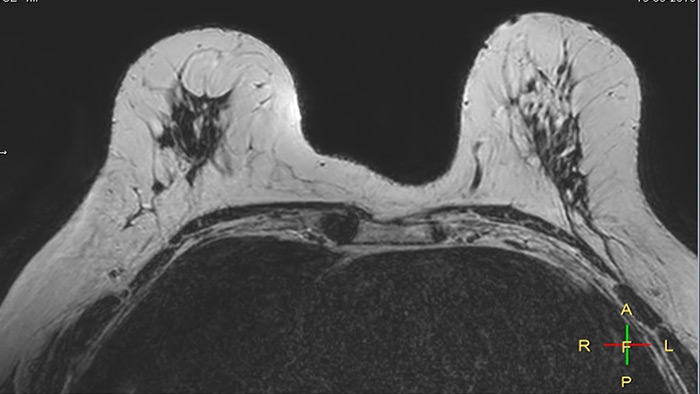

Compressed SENSE, scan time 3:54 min Voxels acq 0.8 x 0.72 x 1.8 mm Voxels recon 0.63 x 0.63 x 0.9 mm

C-SENSE factor 12

SENSE, scan time 6:32 min Voxels acq 0.8 x 0.8 x 1.8 mm Voxels recon 0.63 x 0.63 x 0.9 mm

SENSE factor 3

The time gain with Compressed SENSE was also used to increase resolution in order to help radiologists identify the tumor characteristics more confidently which may be used for a more personalized treatment. For example, in breast imaging, resolution is crucial for visualization of very small lesions. Compressed SENSE allows to scan thinner slices, allowing a 3D isotropic sequence which can provide increased diagnostic confidence for the radiologists.

“The 3D-THRIVE sequence has proven to be important in providing detailed post-processing data to inform on diagnosis and how we care for the patient,” says Ruth Pearson. “Normally, if you want more detail on an MRI scan, the scan takes longer. Previously we’ve had to balance between getting the detail required and how long the patient can lie still. Now with the Compressed SENSE technology, we can get more detail and scan faster.”